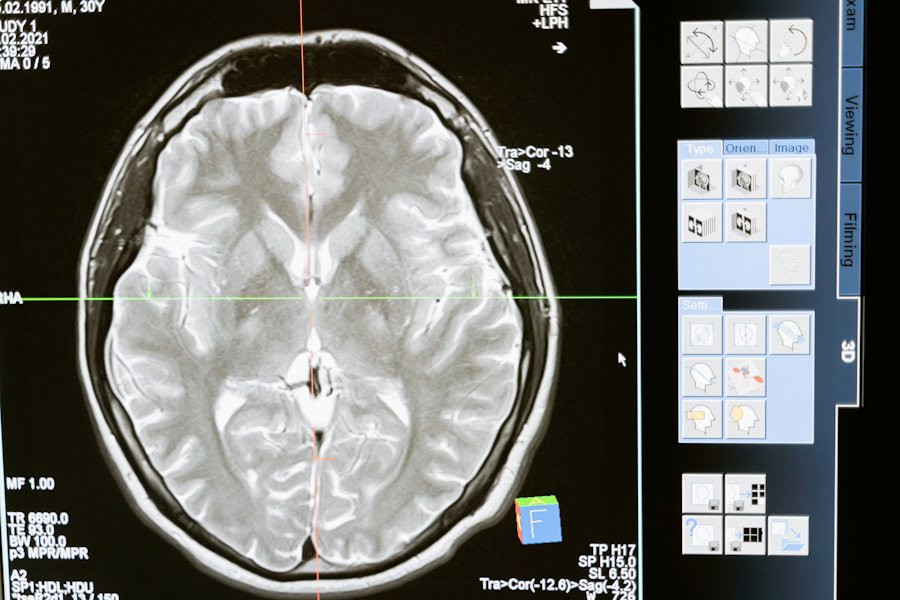

Фото из открытых источников

Ученые сделали важный шаг в понимании того, как мозг интегрирует информацию во время сложных когнитивных процессов, таких как чтение. В новом исследовании, проведенном в University of California, было обнаружено, что нейроны в различных областях мозга синхронизируются, когда человек читает и принимает семантические решения.

Результаты этого исследования опубликованы на портале Nature. Исследователи использовали внутричерепную электроэнцефалографию (ЭЭГ) для наблюдения за активностью мозга у участников эксперимента.